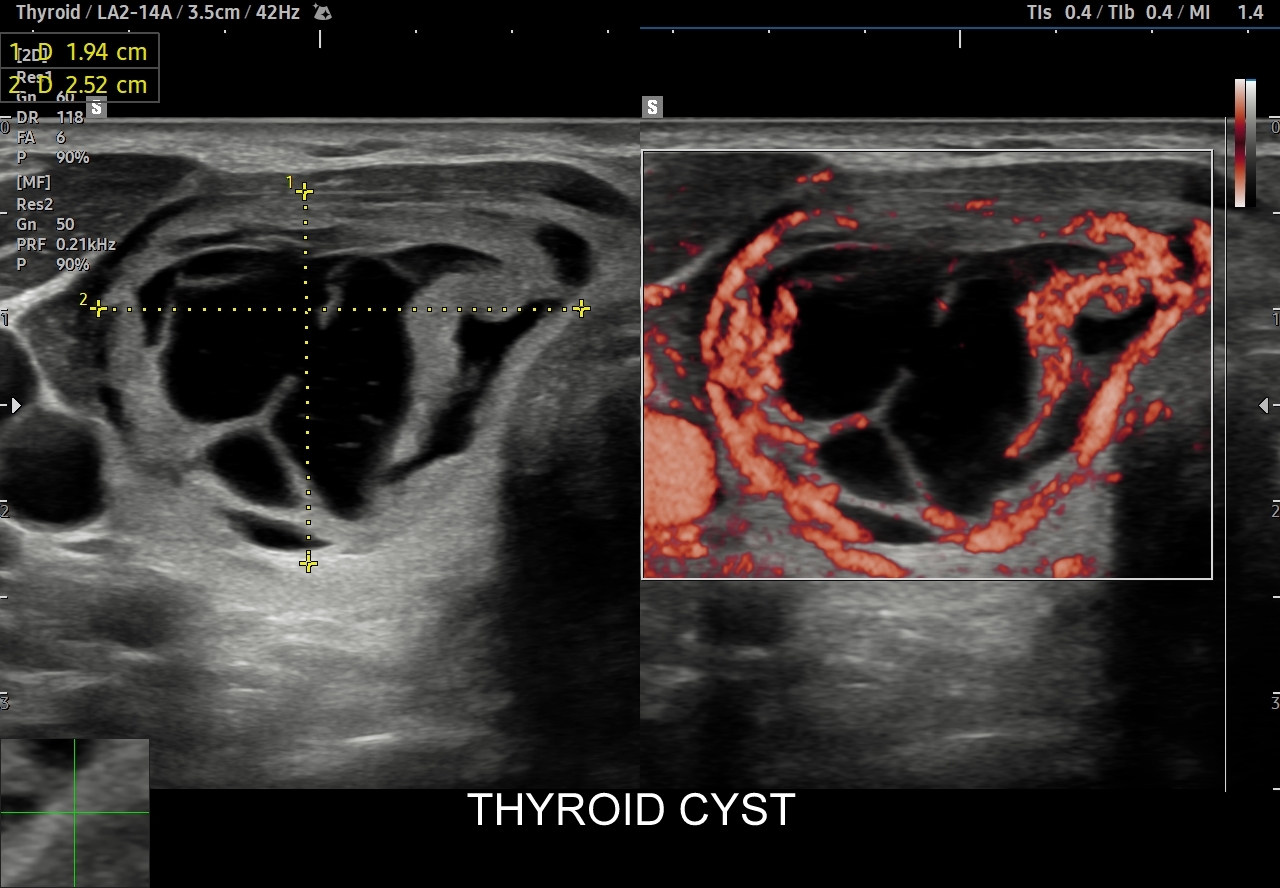

Multiparametryczne badanie USG (MPUS) jest rozwinięciem klasycznego USG tarczycy i szyi pod postacią jednoczasowego zastosowania różnorodnych technologicznie trybów obrazowania USG, zarówno tzw. „nowych”, jak i „starych”. Wśród nowych najważniejszym jest obrazowanie mikrounaczynienia (MVI / MVF), w dalszej kolejności tryb elastograficzny oraz B-flow. Wymienione „nowe” modalności w połączeniu ze „starymi”, przede wszystkim z Dopplerem spektralnym i color-Dopplerem, stanowią rdzeń nowoczesnej ultrasonografii MPUS, gdyż umożliwiają pozyskanie znacznie większej ilości informacji z badania USG szyi w porównywalnym przedziale czasowym, a przez to uzyskanie jego większej wartości diagnostycznej.

Przykładowo badanie MPUS umożliwia różnicowanie guzów, ocenę żywotności tkanek i biologii nowotworów, poprawia obrazowanie dużych naczyń krwionośnych oraz ocenę podejrzanych torbieli. Z kolei zastosowanie badania USG z kontrastem (CEUS), jako kolejnej modalności rozszerzającej MPUS, daje w wyselekcjonowanych przypadkach korzyści m. in. w postaci różnicowania i oceny zmian ogniskowych, czy oceny skuteczności terapii ablacyjnych.